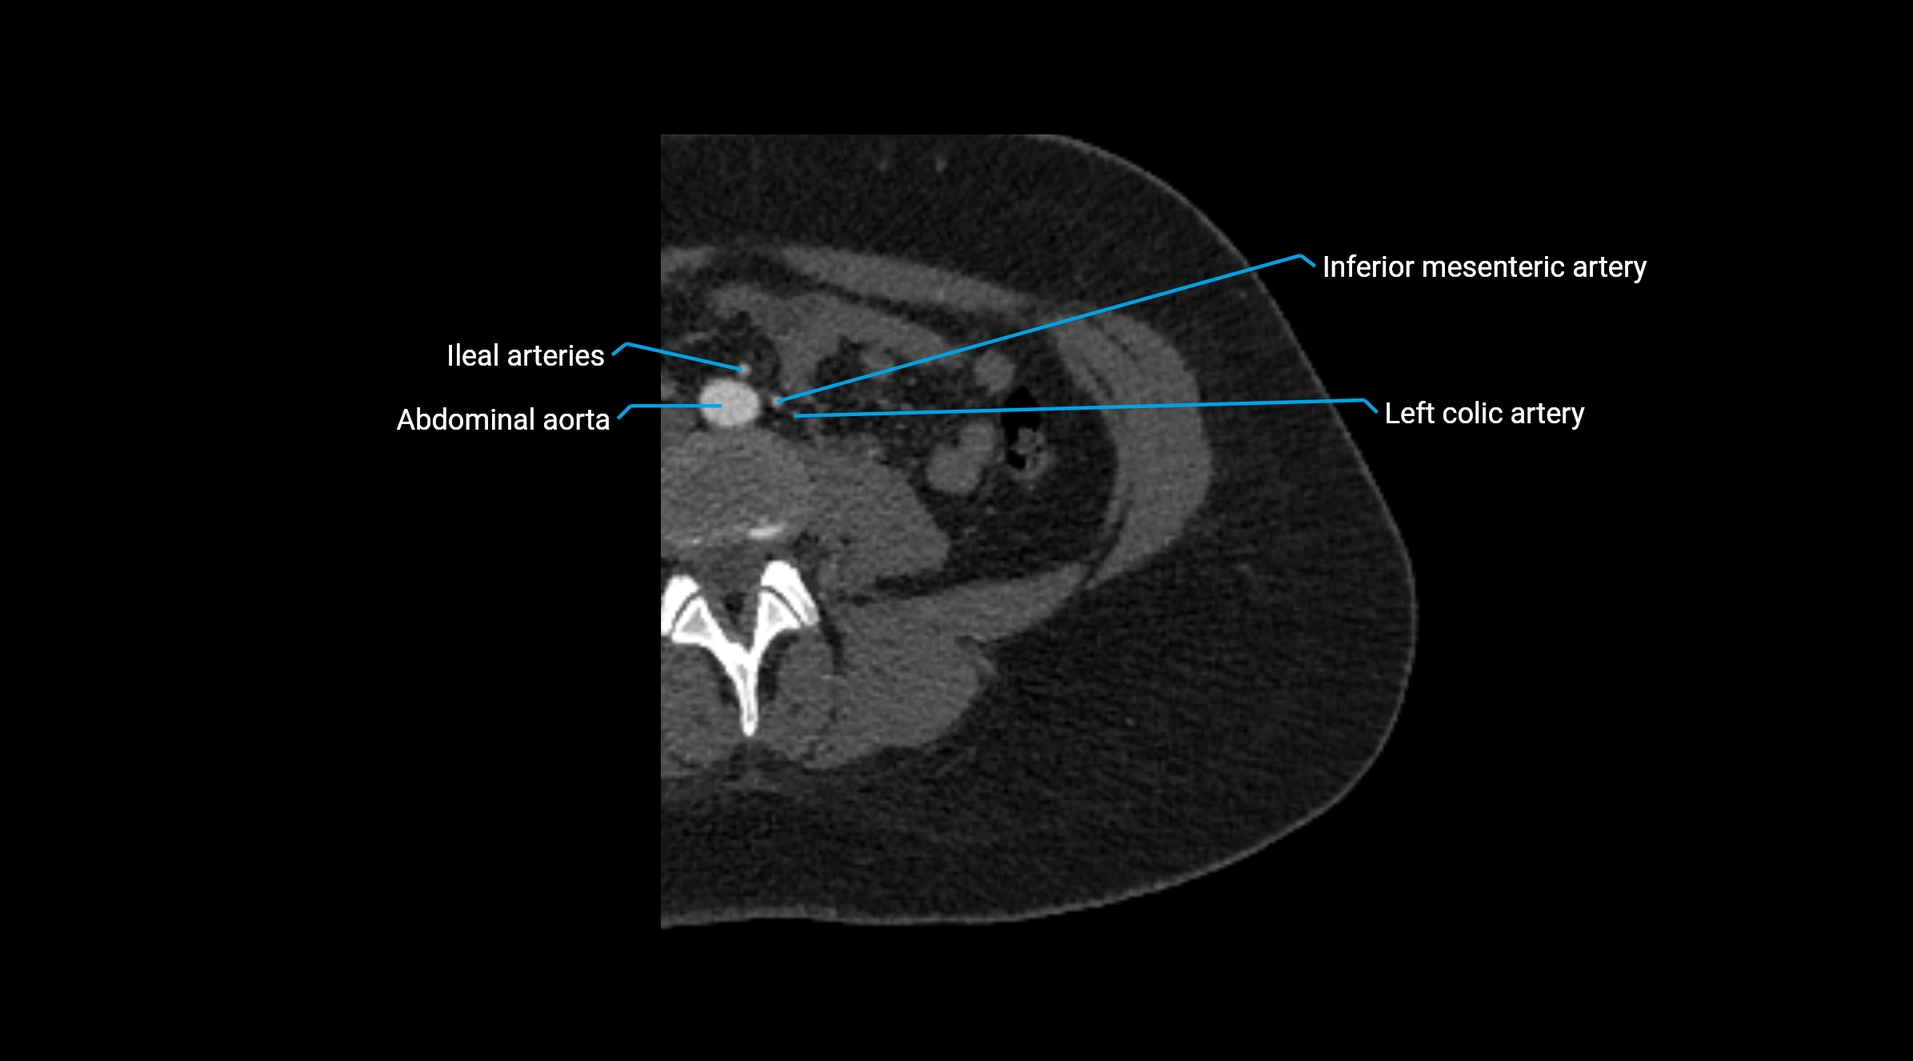

CT Appearance

Non-contrast CT:

• Appears as a tubular soft tissue structure anterior to vertebral bodies

• Calcified atherosclerotic plaques appear as hyperdense foci along the wall

• Useful for screening abdominal aortic aneurysm (AAA) size and mural calcification

Contrast-enhanced CT (CTA):

• Gold standard for abdominal aortic imaging

• Provides excellent detail of lumen, wall, aneurysm, thrombus, and branch vessels

• Multiplanar and 3D reconstructions help in aneurysm measurement, stent graft planning, and dissection evaluation

• Detects acute rupture, traumatic injury, or occlusion with high sensitivity

CT images

image